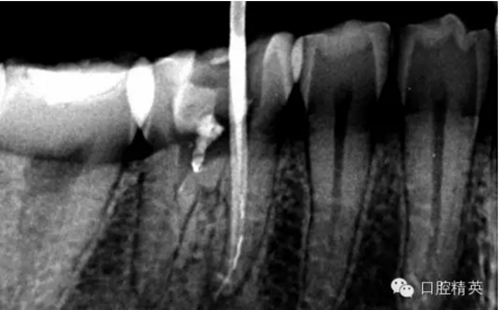

患者,肖某,男,32歲,#36慢性牙髓炎。遠中舌根根尖1/3彎曲而且鈣化不通,我用盡辦法疏通了很久也沒到達WL,(我一直在幻想,要是有超聲系統(tǒng)該多好,可是現(xiàn)實很骨感,我們單位暫時還沒有超聲系統(tǒng)),后來我放棄了,最后的根充片顯示遠中舌根充填物距根尖端2.84mm,屬于欠填范圍(根管內(nèi)充填物距根尖端2mm以上),其它三根根尖1/3鈣化相對沒那么嚴重,根充片顯示屬于恰填范圍(根管內(nèi)充填物距根尖端0.5~2mm)。歡迎網(wǎng)友們針對這個病例提出寶貴的建議!

9.png

10.png